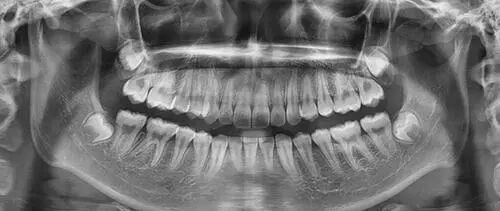

五、为什么根管治疗需要拍多张牙片?

根管治疗时,拍牙片是很有必要的,并且至少要保证3张牙片。

第一张在治疗前,帮助医生了解牙根的基本情况,制定治疗计划;

第二张在治疗中,帮助医生了解治疗情况,如根管预备是否到位等,并制定下一步治疗方案;

第三张是在治疗结束后,帮助判定根管充填质量,发现问题及时补救。